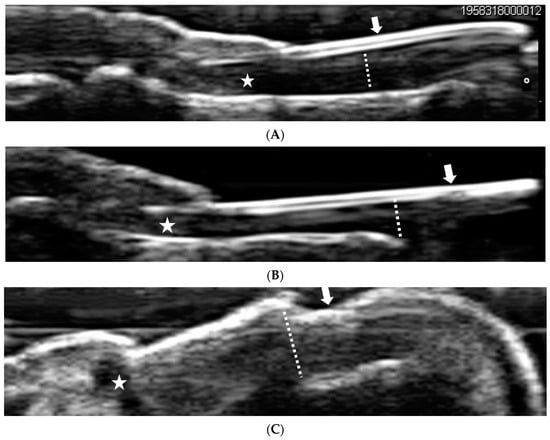

3.2. Ultrasonography Findings at Finger Nails